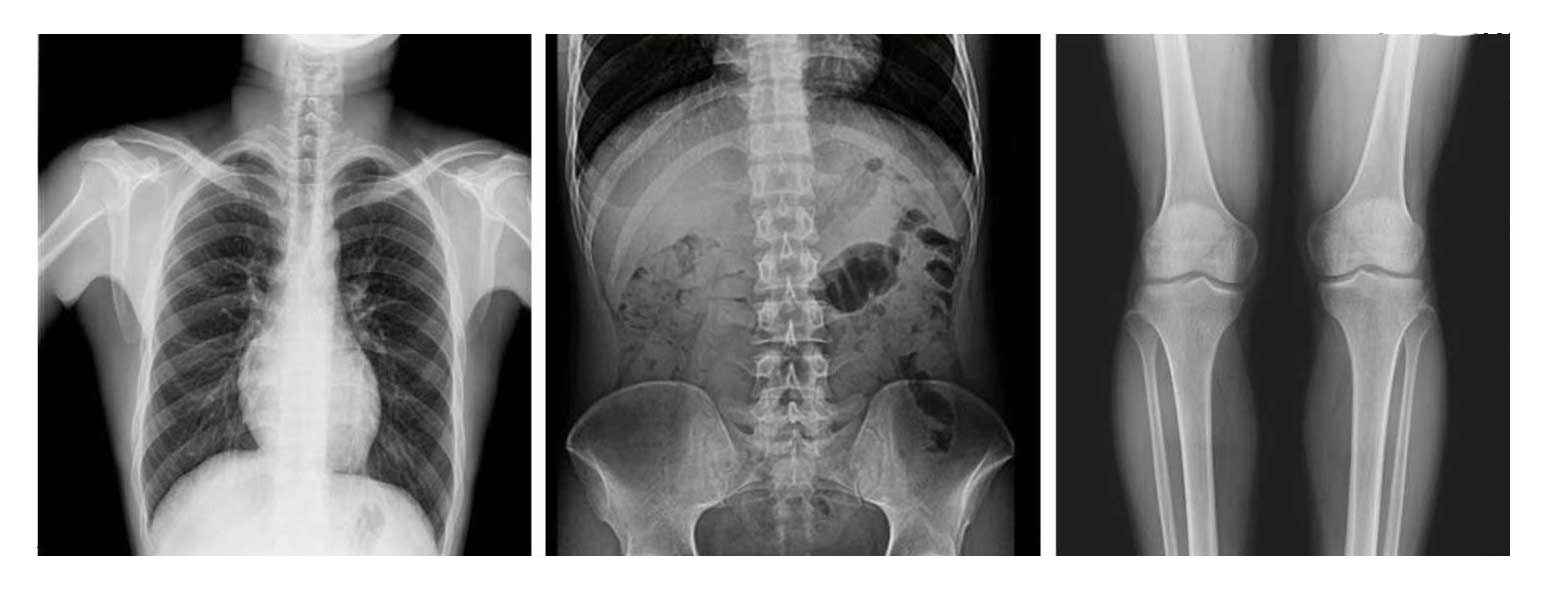

- Применяется для любых клинических рентгенологических исследований, включая специализированную позиционную рентгенографию.

- Высококачественное цифровое изображение с высокой чёткостью и детализацией.

- Автоматическая сшивка изображений (опция): формирование предоперационных планов и оценка послеоперационных результатов (сколиоз, нагрузка на ортопедические изделия, протезирование колена, эндопротезирование тазобедренного сустава).

Рентгенологические исследования: рентгенография больших переломов костей и масштабное физическое рентгенографическое обследование, флюороскопия всех частей тела (грудная клетка, живот и т.п.), пищеводная ангиография, ангиография верхних отделов желудочно-кишечного тракта, полная ангиография желудочно-кишечного тракта, оральная холецистография, внутривенная холангиография, Т-образная холангиография, ЭРХПГ, внутривенная пиелография, гистеросальпингография и т.д.